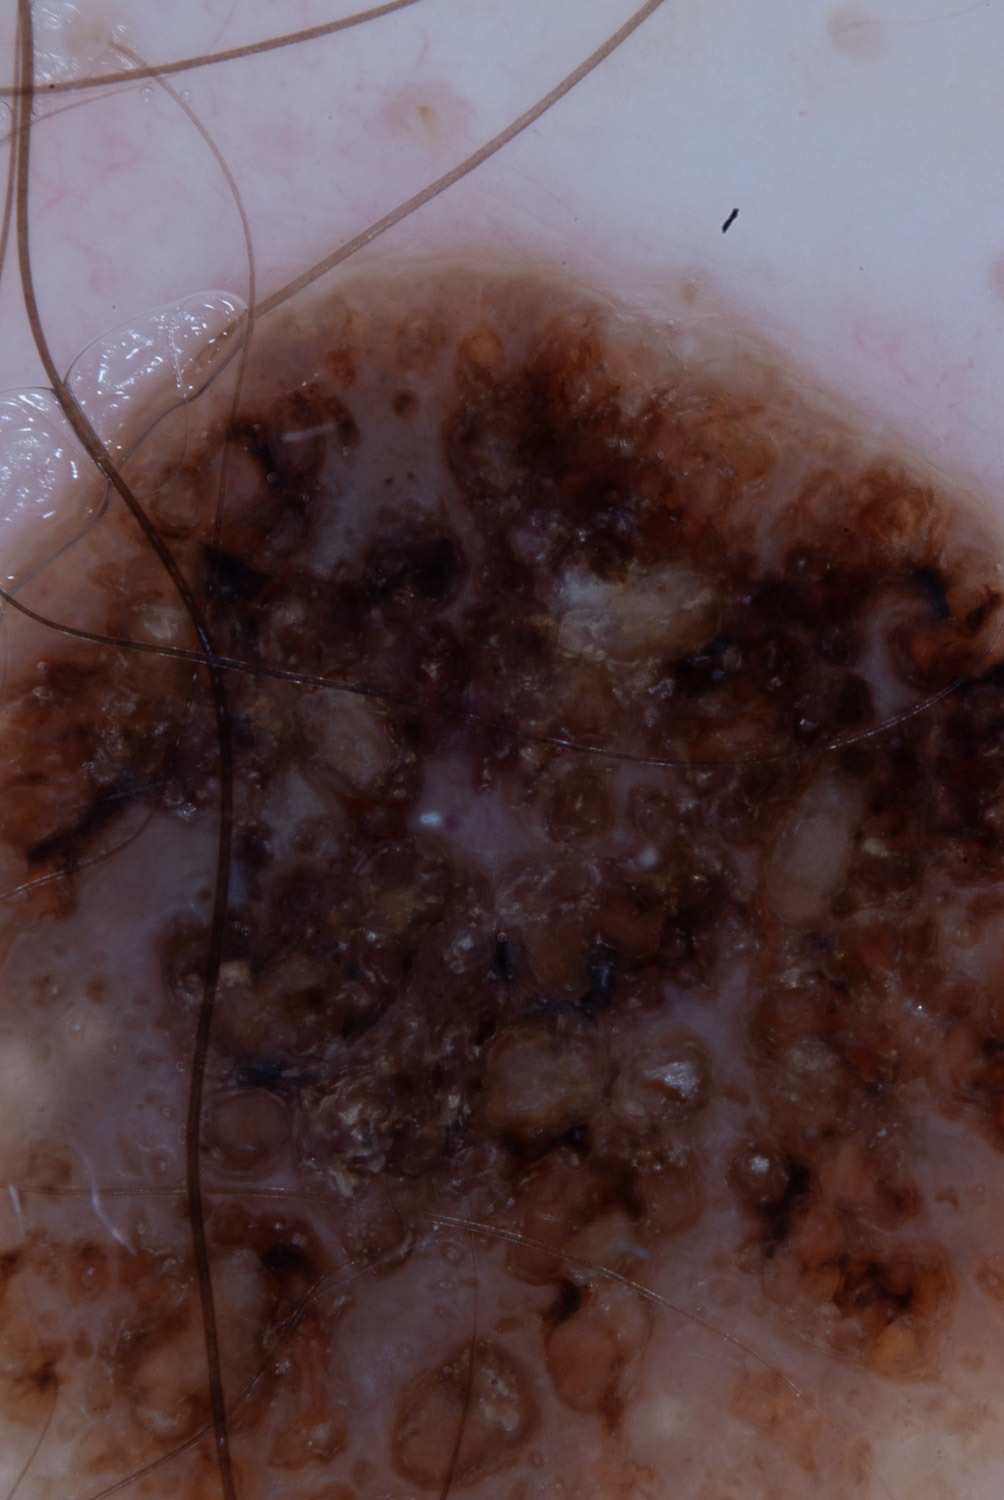

Case: 189